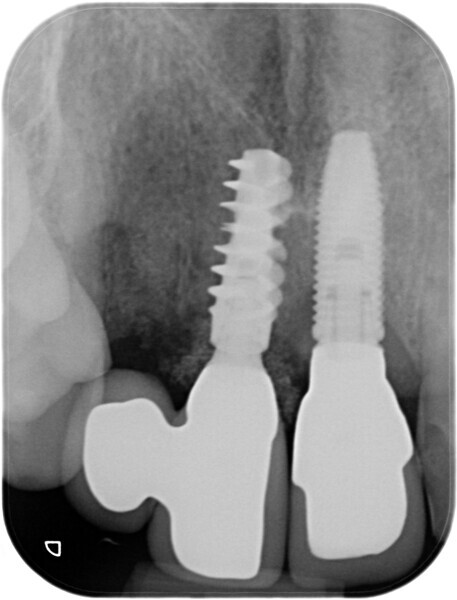

Immediate placement and restoration of a Straumann BLX implant replacing maxillary incisors